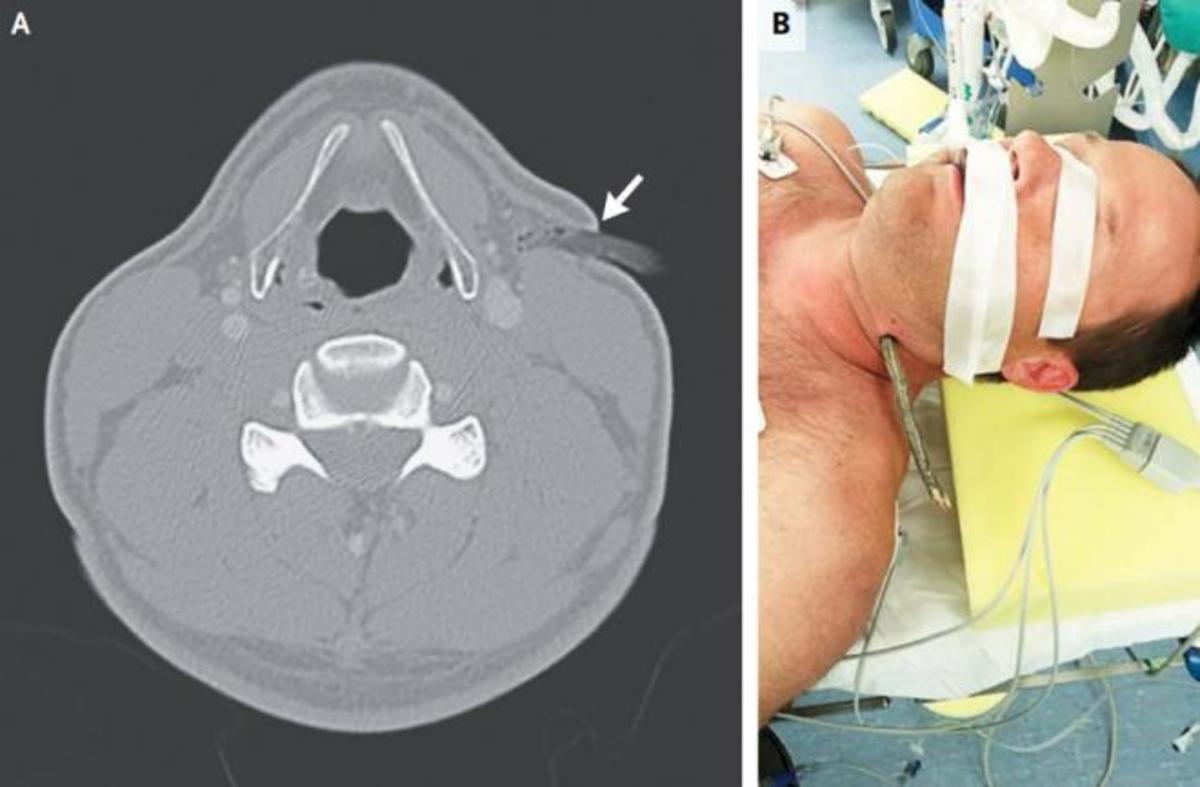

Ο 40χρονος που είχε ατύχημα με το ποδήλατό του και πήγε στα επείγοντα με ένα κλαδί να έχει διαπεράσει τον λαιμό του, χωρίς να του κάνει την παραμικρή σοβαρή ζημιά!